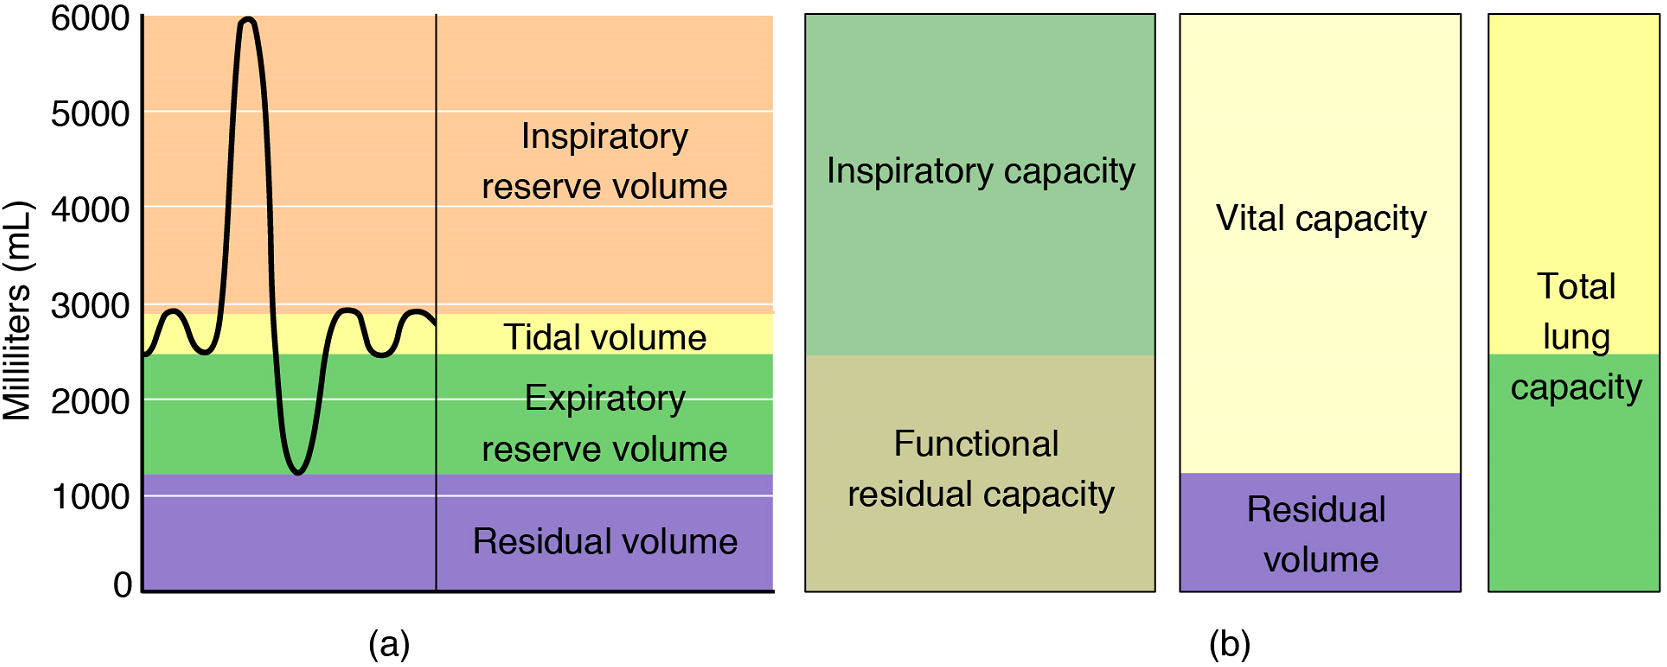

Respiratory volume is the term used for various volumes of air moved by or associated with the lungs at a given point in the respiratory cycle. There are four major types of respiratory volumes: tidal, residual, inspiratory reserve, and expiratory reserve (Figure 15). Tidal volume (TV) is the amount of air that normally enters the lungs during quiet breathing, which is about 500 millilitres (mL). Expiratory reserve volume (ERV) is the amount of air you can forcefully exhale past a normal tidal expiration, up to 1200 mL for men. Inspiratory reserve volume (IRV) is produced by a deep inhalation, past a tidal inspiration. This is the extra volume that can be brought into the lungs during a forced inspiration. Residual volume (RV) is the amount of air left in the lungs if you exhale as much air as possible. This air prevents alveoli collapsing in on themselves, which makes it possible for alveoli to re-inflate during inhalation. Without residual volume, pulmonary ventilation would cease. Respiratory volume is dependent on a variety of factors, and measuring the different types of respiratory volumes by using a spirometer to generate a spirogram can provide important clues about a person’s respiratory health (Figure 15).

Respiratory capacity is the combination of two or more selected volumes, which further describes the amount of air in the lungs during a given time. For example, total lung capacity (TLC) is the sum of all of the lung volumes (TV + ERV + IRV + RV), which represents the total amount of air a person can hold in the lungs after a forceful inhalation. TLC is about 6000 mL air for men, and about 4200 mL for women. Vital capacity (VC), which is between 4000 and 5000mL, is the amount of air a person can move into or out of his or her lungs, and is the sum of all of the volumes except residual volume (TV + ERV + IRV).

Inspiratory capacity (IC) is the maximum amount of air that can be inhaled past a normal tidal expiration, and is the sum of the tidal volume and inspiratory reserve volume. On the other hand, the functional residual capacity (FRC) is the amount of air that remains in the lung after a normal tidal expiration; it is the sum of expiratory reserve volume and residual volume (see Figure 15).

In addition to the air that creates respiratory volumes, the respiratory system also contains anatomical dead space, which is air that is present in the airway that never reaches the alveoli and therefore never participates in gas exchange. Alveolar dead space involves air found within alveoli that are unable to function, such as those affected by disease or abnormal blood flow. Total dead space is the anatomical dead space and alveolar dead space together, and represents all of the air in the respiratory system that is not being used in the gas exchange process.